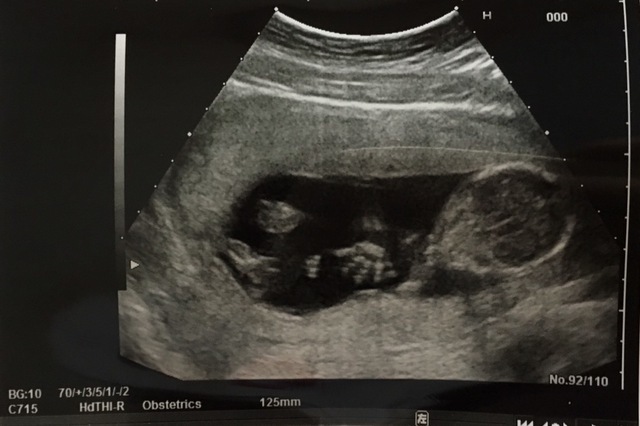

31週0日(31w0d・男の子)|京吾くんママ さん(21歳)

エコー写真撮影時のエピソード:

いつもエコーの時は顔を腕で隠していた息子ですが、初めて顔を見せてくれました。パパにそっくりで笑っちゃいましたが、この子がお腹の中にいるんだと思ったら余計に愛おしくなりました。産まれてからも寝顔はこのままです。(笑)